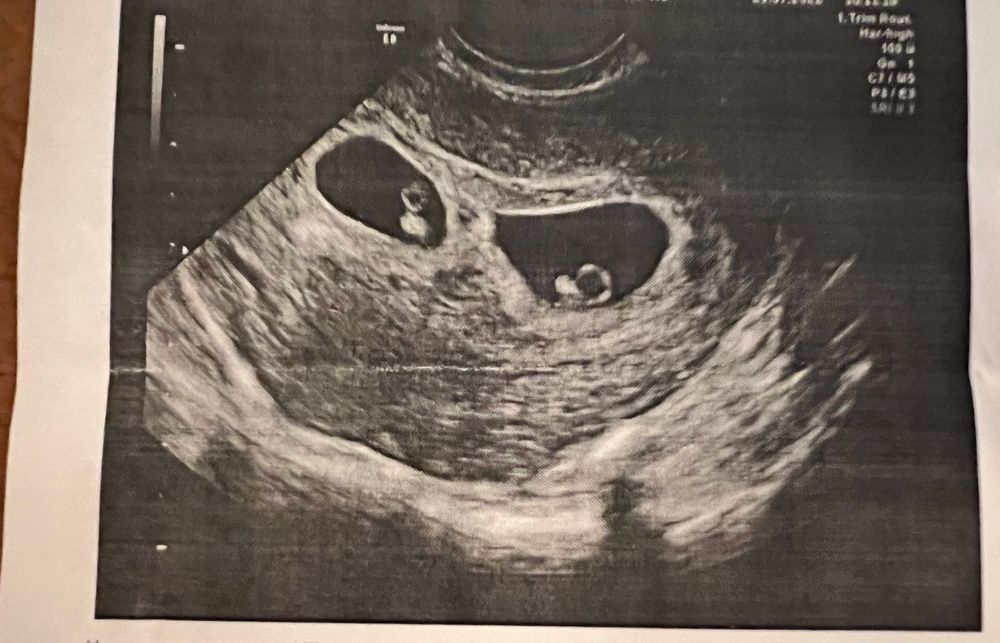

26 дпп узи второе (первое было на 20 дпп)

Врач сказал все Окей ,поэтому решила расслабиться и не т**хать себе мозги 😅

Какая красота😻

Ух ты какие криветочки малюсенькие))) спокойной беременности вам и лёгких родов 🤩